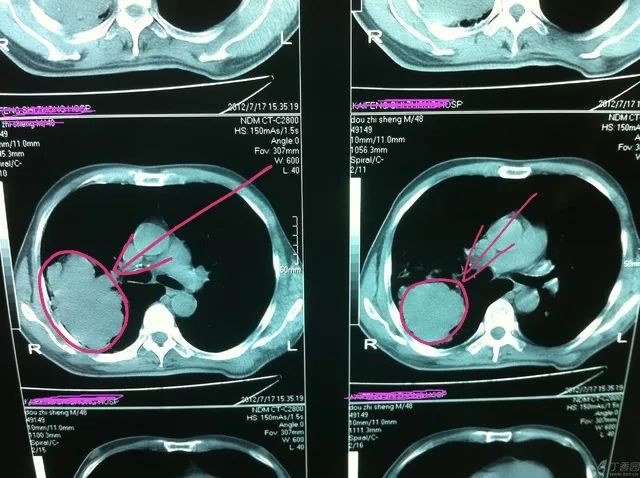

方框内箭头所指白色区域就是肺结节,左右各一个,比较小(直径大概5毫米~1厘米),其他区域是正常的肺组织、血管、器官和心脏等正常结构。

箭头所指红色圆圈内的就是肺占位,比较大(直径大约5~8厘米)